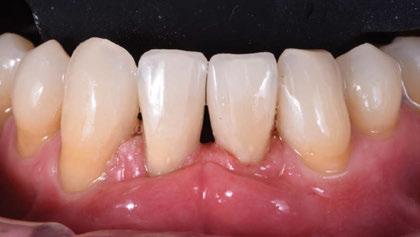

Figura 1. Caso clínico 1. Situación clínica basal de una paciente que presenta recesiones gingivales con pérdida de inserción interproximal en el quinto sextante. A la exploración se observa una profundidad de sondaje incompatible con salud en centro-vestibular del diente en posición de 41, presumiblemente combinado con una dehiscencia ósea.

Paciente de 32 años de edad que acude a la consulta preocupada por la situación de su diente en posición de 41. Le preocupa tanto a nivel de salud como a nivel estético. Además, refiere incapacidad para llevar a cabo un correcto cepillado de esa zona e hipersensibilidad dental.

A la exploración clínica presenta una recesión RT3 (23) en el diente en posición de 41. Además, carece de una banda de encía queratinizada adecuada (≥2mm) y presenta una reducción significativa de la